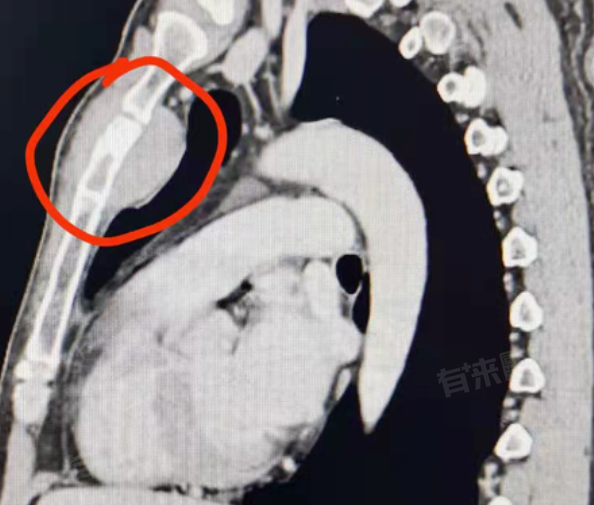

1、胸骨体部:胸骨体部是胸骨肿瘤最常见的发生部位,胸骨体部位于胸骨中间部分,连接胸骨柄和剑突。由于胸骨体部是胸骨的主要组成部分,其血液供应丰富,细胞代谢活跃,因此容易发生肿瘤。胸骨体部肿瘤可能起源于骨膜、骨软骨或骨髓等组织,既有可能是原发性肿瘤,也有可能是其他部位肿瘤转移而来。

2、胸骨柄与剑突:除了胸骨体部,胸骨柄和剑突也是胸骨肿瘤可能出现的部位,胸骨柄位于胸骨的最上端,与锁骨和第一肋软骨相连;剑突则位于胸骨的最下端,是一块软骨组织。这些部位虽然相对较小,但同样有可能发生肿瘤。特别是剑突部位,由于其位置较为表浅,有时可以通过触诊发现肿块。

3、肋骨:虽然胸骨肿瘤主要出现在胸骨体部及其周围结构,但肋骨也是胸部肿瘤常见的发生部位之一。肋骨肿瘤可能起源于肋骨的骨膜、骨质或骨髓等组织,既有可能是原发性肿瘤,也有可能是其他部位肿瘤转移而来,肋骨肿瘤可能表现为肋骨局部隆起、疼痛或压痛等症状。